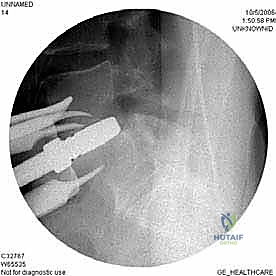

الخطوة 4: التحضير وزراعة القفص (Implant Insertion)

يتم قياس الفراغ المتبقي بدقة لاختيار الحجم المثالي للقفص الجراحي (Cage). يُصنع هذا القفص عادة من مادة PEEK أو التيتانيوم، ويتم حشوه بمادة عظمية (طعم عظمي ذاتي من المريض، أو طعم صناعي، أو بروتينات محفزة لنمو العظم BMP). يتم إدخال القفص بقوة في الفراغ، مما يؤدي فوراً إلى استعادة ارتفاع القرص الطبيعي وتوسيع المخارج العصبية (تخفيف الضغط غير المباشر).

الخطوة 5: التثبيت (Fixation)

لضمان أقصى درجات الثبات والسماح للعظم بالاندماج بمرور الوقت، يتم تثبيت القفص باستخدام شريحة معدنية صغيرة ومسامير من التيتانيوم تُثبت في الأجسام الفقرية من الأمام. في بعض الحالات، قد يرى الدكتور هطيف ضرورة إضافة تثبيت خلفي بمسامير عبر الجلد (Percutaneous Pedicle Screws) لزيادة الدعم.